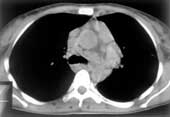

- Передние внутримаммарные л/узлы (Рис. 1), которые в норме не визуализируются, располагаются по ходу внутренней артерии молочной железы. Поражаются часто при раке молочной железы, реже при лимфогрануломатозе и лимфосаркоме.

Рис. 1. Передние внутримаммарные л/узлы.